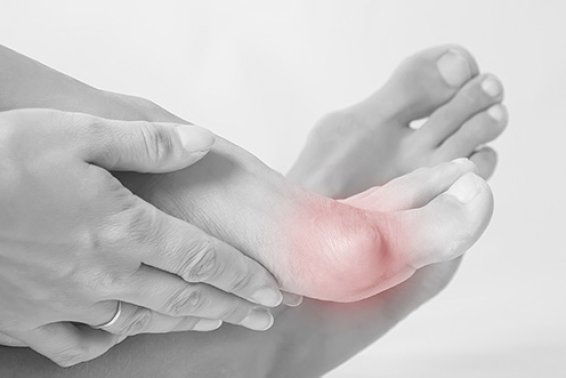

Bunions or “a stone in my shoe”

Bunions are widespread in the population and definitely one of the most prevalent conditions in our foot and ankle clinic. Some ...

What is a bunion? Is surgery needed?

A bunion, medically known as hallux valgus, is a deformity characterised by a lateral deviation of the big toe towards the ...